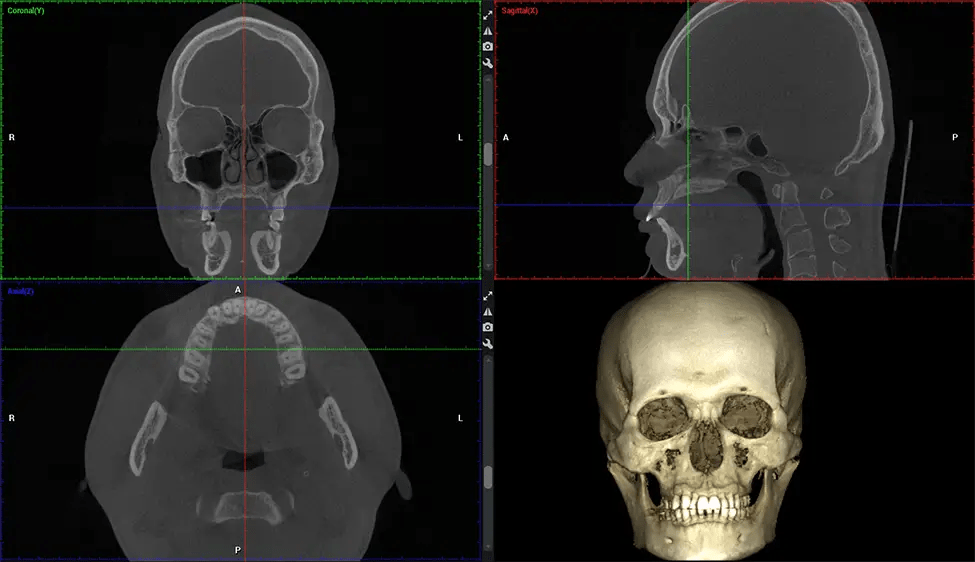

Cone Beam Computed Tomography (CBCT) is an advanced imaging technique used in dentistry and maxillofacial surgery to obtain detailed 3D images of the oral and maxillofacial structures. At Dr G Dental Studio, our CBCT scanners utilize a cone-shaped X-ray beam and a specialized detector to capture images from different angles. A computer then combines these images to create a 3D representation of the patient’s oral anatomy.

There are many benefits to using CBCT technology, especially compared to the traditional 2D X-ray format. One of the most significant advantages of CBCT scans is that they provide much more information than traditional X-rays. A scan lets your dentist see images from all angles of your jaw and mouth, including your sinuses, nasal cavity, cheekbones, and other surrounding areas. This added information helps your dentist craft a comprehensive treatment plan that addresses all aspects of your oral health.

Planmeca Viso G7 CBCT ( Cone Beam CT Scan ) is designed to surpass the demands of industry leaders, specialists, and large institutions. It’s has a large ø25×30 cm sensor with four built-in cameras. It can capture unlimited volume sizes from a ø3×3 cm to a ø30x30cm volume capturing the skullcap through C7 on the cervical spine. The Planmeca Viso G7 offers the industry’s largest single volume scan of ø30×19 cm. It’s poised to handle advanced imaging modalities such as Planmeca ProFace® and Planmeca 4D™ Jaw Motion technology. The occipital head support allows an unimpeded view of facial tissue.